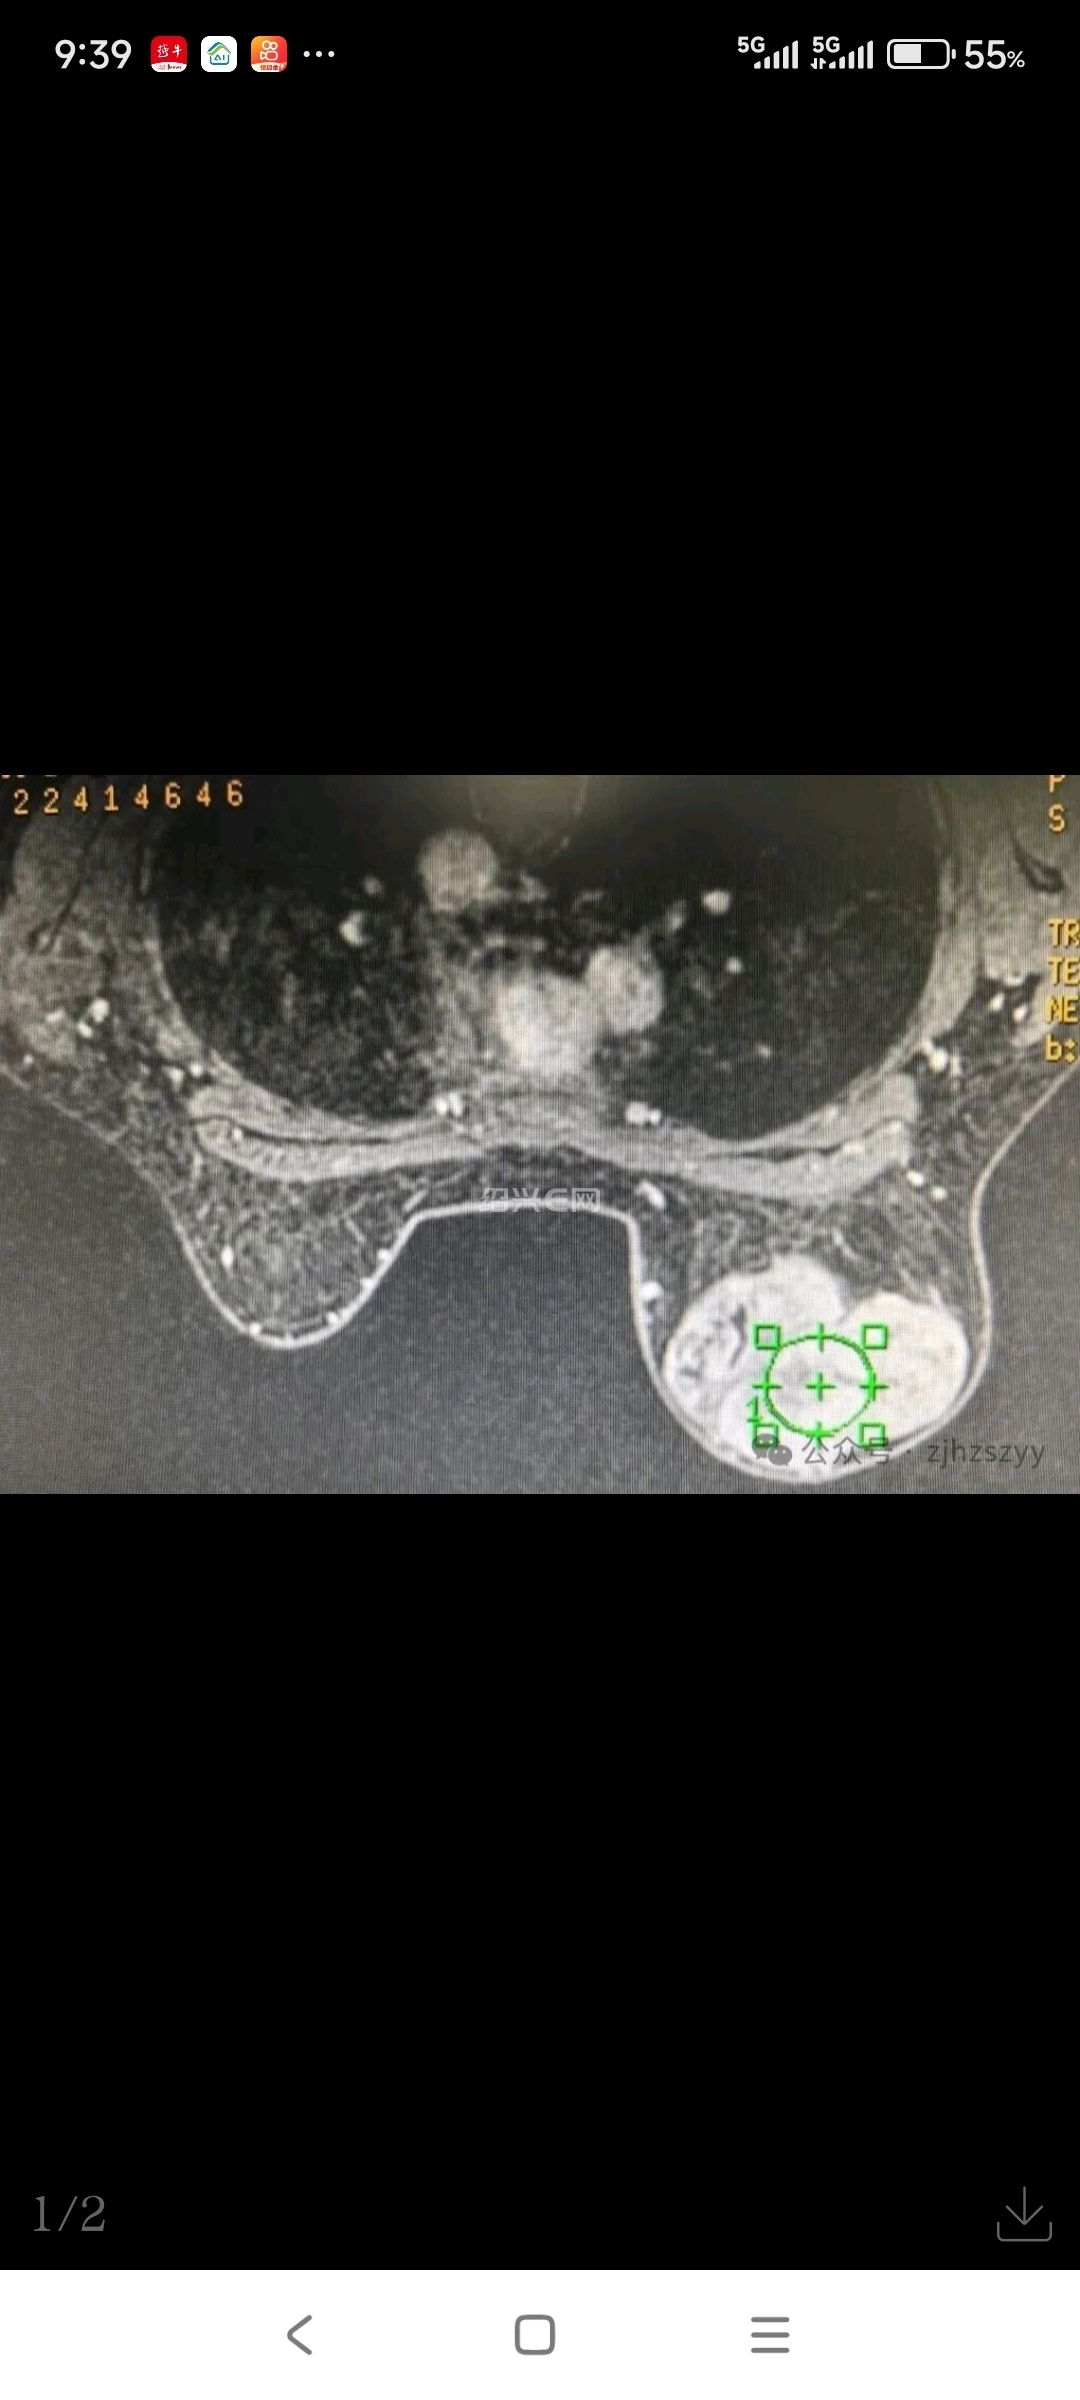

“就是自己摸到的,一开始没在意,没想到现在变这么大了……”入院后检查发现,小刘的右乳肿块已达10cm×12cm,几乎占据整个乳房,外观上右乳已明显大于左侧。医生结合检查情况,建议她尽快手术切除并进行病理检查。

考虑到小刘年轻,对乳房外观有需求,医生在与她充分沟通后,制定了个性化的手术方案:选择在乳房下缘做仅4cm的小切口,既能完整切除肿块,又能最大程度隐藏疤痕,切除后进行美容缝合,再植入假体修复乳房形态,术后完全看不出手术痕迹,这让小刘悬着的心放下了大半。

术后病理提示,小刘的肿瘤是良性叶状肿瘤,后续只需遵医嘱定期复查即可。